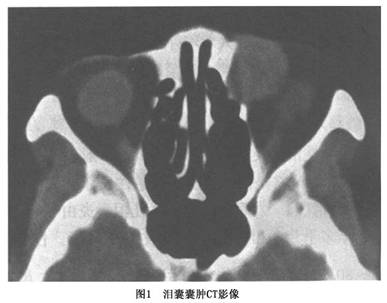

(2)黏液囊肿(mucocele):泪囊壁失去张力而扩张,分泌物在泪囊内积聚形成囊肿。在内眦韧带下方一有波动的突起,挤压时有胶冻样透明或乳白色的分泌物从泪小管回流或压入鼻腔。一旦因为炎症上、下泪小管闭塞,囊肿将继续扩张,在皮下形成相当大的略呈蓝色的囊性肿块,但不与皮肤粘连CT扫描显示泪囊区为一囊性占位病变,中低密度,因内侧为骨性结构病变多向眶内突出(图1)。